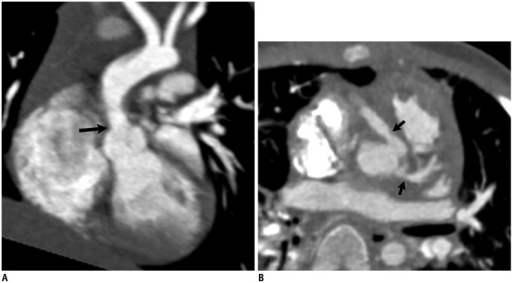

- Imaging

- For AS and AR: 2D echocardiogram with Doppler study

- Measuring aortic jet velocity, mean aortic valve pressure gradient, and aortic valve area